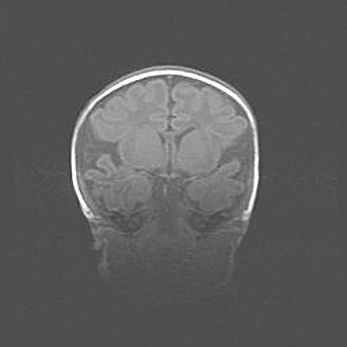

Церебральная ишемия II.

Возраст: 5 дней

Вес: 3400 г

Пол: женский

Окружность головы: 35 см

Срок гестации: 39 недель

Церебральная ишемия – это заболевание, характеризующееся недостаточностью (гипоксией) либо полным прекращением (аноксией) снабжения мозга кислородом по причине закупорки одного или нескольких сосудов. Это приводит к  что метаболическим расстройствам различной степени тяжести в тканях головного мозга, развитию коагуляционных некрозов и гибели нейронов.